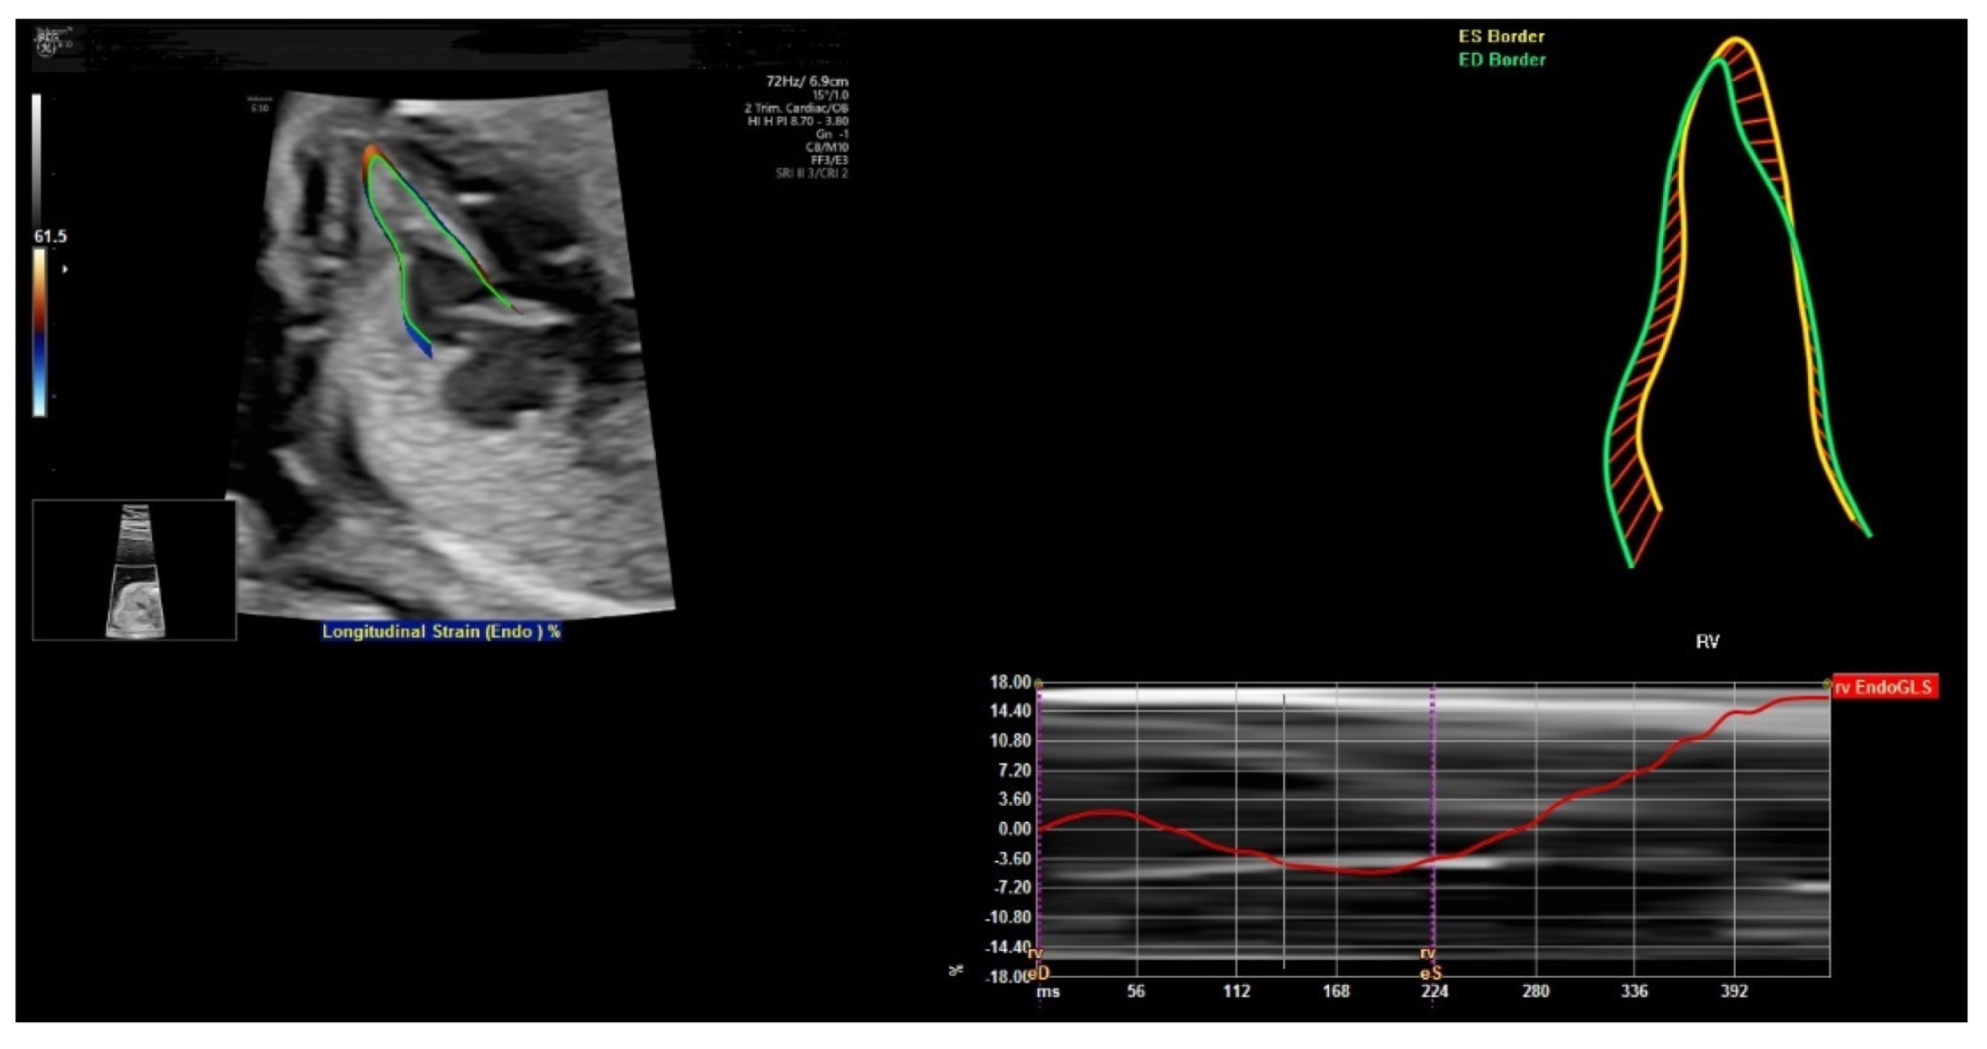

6. FetalHQ

FetalHQ, a novel heart and vascular analysis software, can allow assessment of the fetal heart shape, size, and contractibility by using speckle tracking to analyze the motion of multiple points of the fetal heart [62] (Figure 13). The global sphericity index (SI) is a simple measurement of cardiac contractility, and it is equal to (end-diastolic mid-basal–apical length)/transverse length [63]. For 24-segment sphericity index, SI is computed for each of the 24 end-diastolic transverse segments, which are distributed from the base to the apex of each ventricle, as well as the end-diastolic mid-basal–apical length [62].

Figure 13.

FetalHQ assessment of the fetal heart shape, size, and contractibility by using speckle tracking to analyze the motion of multiple points of the fetal heart at 20 weeks’ gestation.

This 24-segment sphericity index is a comprehensive method to assess the shape of ventricular chambers [62]. The SI for each segment was independent of gestational age and fetal biometry. The SI of the right ventricle was lower than that of the left ventricle for segments 1–18. This index can be used when discordance between the size of the atrial and/or ventricular cardiac chambers is found. Abnormal SI values are found in the fetuses with cardiac abnormalities such as coarctation of aorta, pulmonary stenosis, and fetal growth restriction [62]. Abnormal SI values are associated with increased risk of perinatal complications and childhood and/or adult cardiovascular disease [64].

While the initial results are promising, a recent review of 23 studies showed conflicting results concerning the development of strain and strain rate during gestation [65]. Large longitudinal cohort studies with a standard protocol are needed to obtain reference values for fetal cardiac deformation in uncomplicated pregnancies [65]. A recent systematic review also showed heterogeneous results concerning gestational age and Doppler profiles. Large prospective longitudinal cohort studies are required to assess the clinical significance of deformation measurements of the fetal heart in growth restricted fetuses and normal fetuses [66].